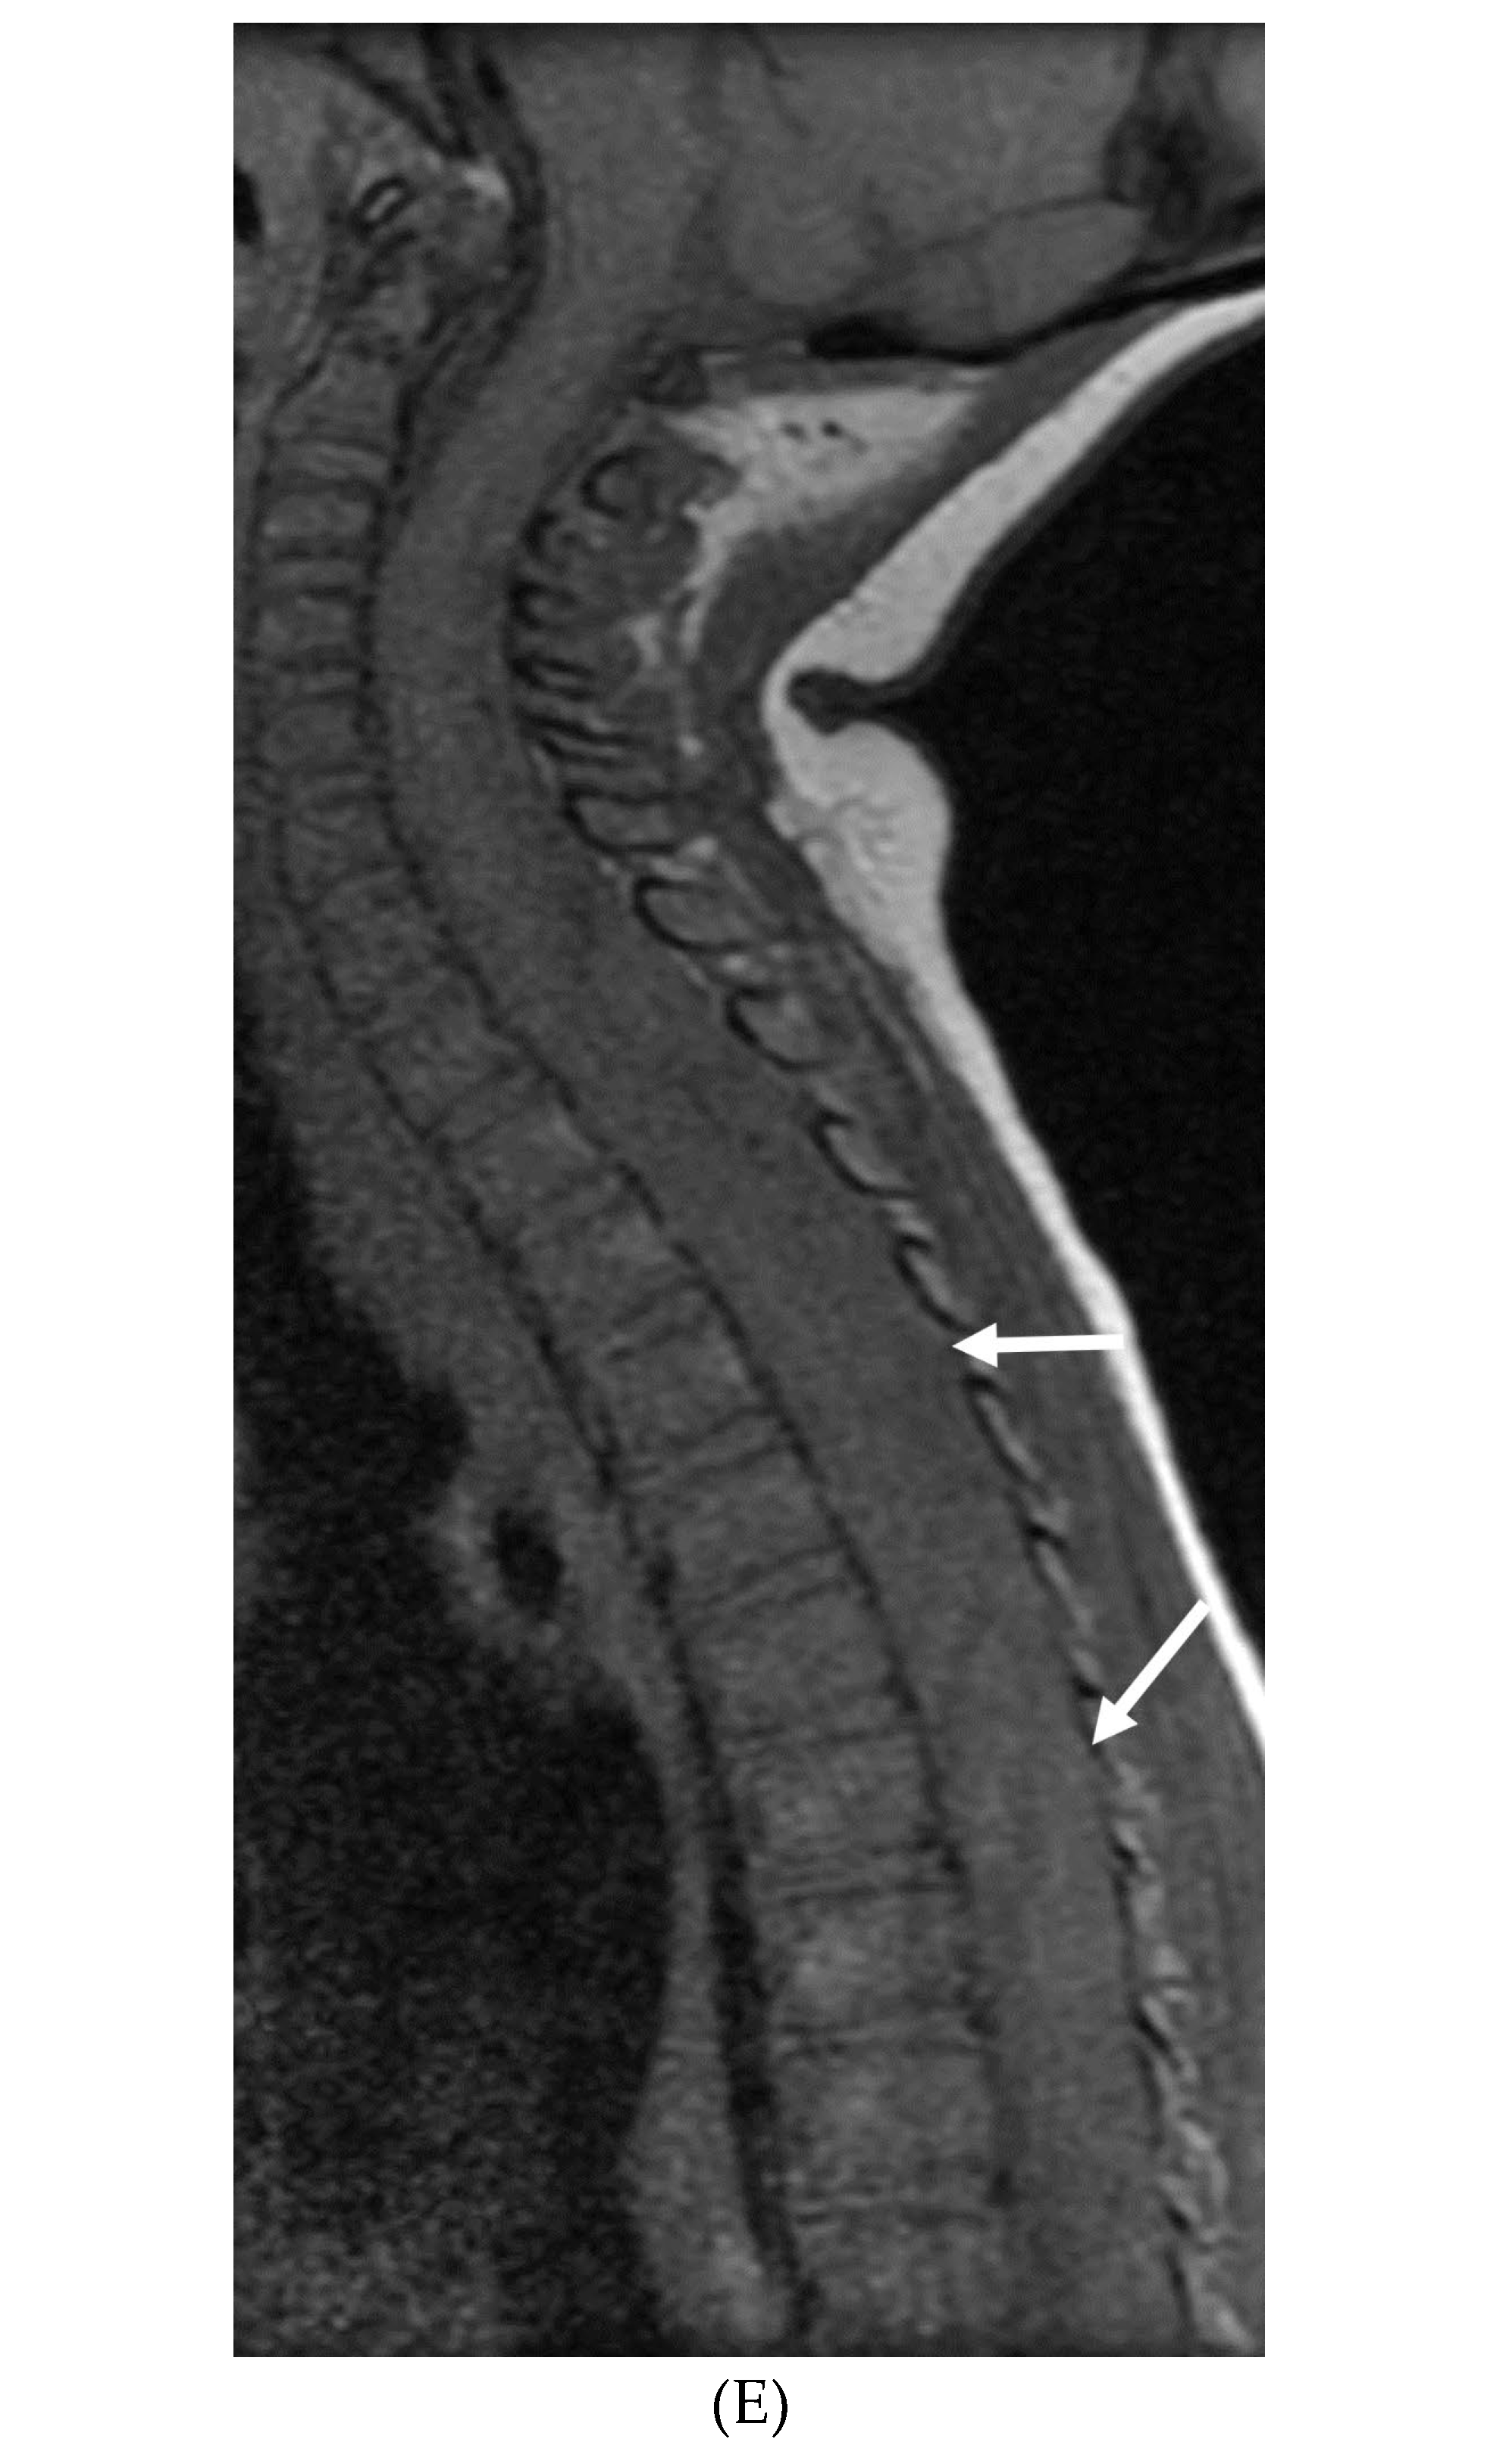

INTRACRANIAL HYPOTENSION (IH)

- Peterson EE, Riley BL, Windsor RB. Pediatric Intracranial Hypotension and Post-Dural Puncture Headache. Semin Pediatr Neurol. 2021 Dec;40:100927. Epub 2021 Sep 3. PMID: 34749914. [CrossRef]

- Schievink WI, Maya MM, Louy C, Moser FG, Sloninsky L. Spontaneous intracranial hypotension in childhood and adolescence. J Pediatr. 2013 Aug;163(2):504-10. Epub 2013 Feb 28. PMID: 23453548. [CrossRef]

- Shah LM, McLean LA, Heilbrun ME, Salzman KL. Intracranial hypotension: improved MRI detection with diagnostic intracranial angles. AJR Am J Roentgenol. 2013 Feb;200(2):400-7. PMID: 23345364. [CrossRef]

- Yuh EL, Dillon WP. Intracranial hypotension and intracranial hypertension. Neuroimaging Clin N Am. 2010 Nov;20(4):597-617. PMID: 20974378. [CrossRef]

- Medina JH, Abrams K, Falcone S, Bhatia RG. Spinal imaging findings in spontaneous intracranial hypotension. AJR Am J Roentgenol. 2010 Aug;195(2):459-64. PMID: 20651205. [CrossRef]